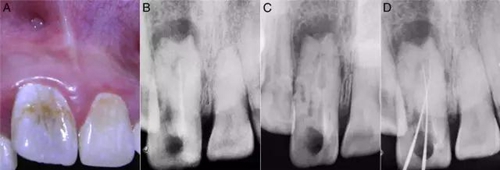

檢查:11曾做過根管治療、叩診(+)。冠修復脫落,暴露根管口和齲壞的牙體組織,還有近遠中腭溝深齲延伸至釉牙骨質(zhì)界。11較21尺寸要大并向唇側(cè)傾斜、冠1/3突出,中間部分凹陷。唇前庭有局部的棕色斑點和竇道開口(圖1A)。牙髓電活力測試和冷熱診均呈陰性反應。

X線檢查:11暗示有牙內(nèi)陷的發(fā)育畸形,冠根呈桶狀。根管復雜但只有一個根尖孔,先前的根管充填并不徹底。還有中等大小的根尖周病變(圖1B)。

圖1:A:11外部形態(tài);B:11之前的根管治療;C:牙膠去除后,牙內(nèi)陷的形狀、可以看出復雜根管和盲袋;D:DM傾斜走形和MI在根尖區(qū)重疊。